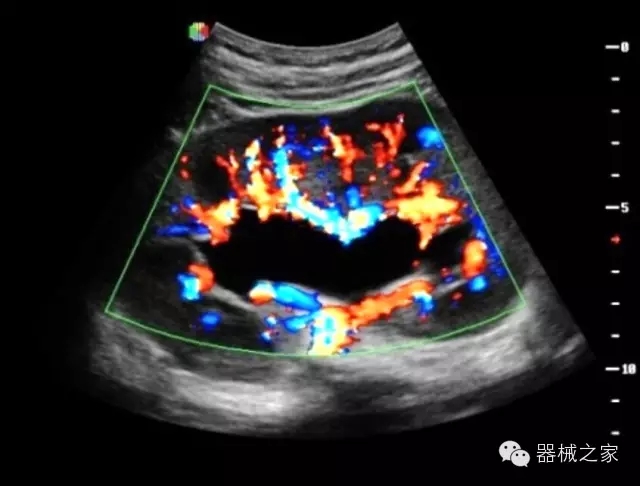

臨床圖片賞析

·獨有的RF平臺提高微小細節(jié)顯示、圖像對比度和邊界清晰度;

·特有的XCEN探頭,超寬的帶寬,表現(xiàn)更高分辨率和對比度;

·單晶純凈波探頭提供更佳的穿透力和彩色敏感度;

·完整的3D/4D臨床應用,STIC, MCUT 和Auto NT等滿足產(chǎn)科所有應用;

·更高的HQ羊膜腔鏡成像技術精細觀察每一個暗區(qū)細節(jié);

·飛依諾特有心臟純凈波探頭提供更好的穿透力和彩色敏感度,以及結合TView梯形拓展改善困難病人深部組織成像;

·獨有RF敏感血流使得心臟血流完美呈現(xiàn);